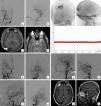

A 36-year-old male presented to the Emergency Department with clinical symptoms of blurred vision of progressive onset of two years of evolution. The ophthalmological examination revealed the existence of bilateral papilledema. Using cranial computed tomography and magnetic resonance imaging, the presence of a right occipital pial arteriovenous malformation was certified. Arteriographically, pial arterial contributions dependent on the right middle cerebral artery and the right posterior cerebral artery were identified. Venous drainage was located at the level of the superior sagittal sinus. An associated right transverse sinus stenosis was also identified. The existence of secondary intracranial hypertension was corroborated by monitoring with an intracranial pressure sensor. An interventional procedure was carried out consisting of embolization of the arterial supplies of the lesion using Onyx®. The clinical-radiological findings after the procedure were favorable: the papilledema disappeared and complete exclusion of the malformation was achieved. A new intracranial pressure measurement showed resolution of intracranial hypertension. Subsequent regulated radiological controls showed complete exclusion of the malformation up to 5 years later.